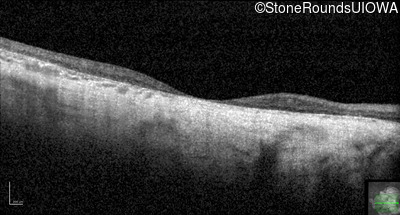

Visit at age: 76 years

Optical Coherence Tomography - Left - 20/150

Exemplar / OCT Stack

OCT Stack